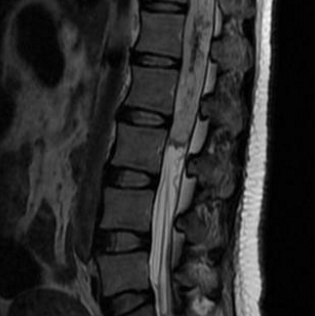

脊髓海綿狀血管瘤(spinal cavernous malformation)可能對(duì)不少人來(lái)說(shuō)很陌生,但其病例增長(zhǎng)也引起人們的關(guān)注,它是一種少見(jiàn)的脊髓血管疾病。脊髓海綿狀血管瘤的誘發(fā)因素通常有先天性血...

脊髓髓內(nèi)腫瘤能治好嗎?脊髓髓內(nèi)腫瘤是一種少見(jiàn)的中樞神經(jīng)系統(tǒng)腫瘤,其獨(dú)特的挑戰(zhàn)是由于周?chē)M織的雄辯...

脊髓腫瘤該怎么治療?髓內(nèi)腫瘤占成人全部椎管內(nèi)腫瘤的20%,占兒童全部椎管內(nèi)腫瘤的35%,治療難度大較大...

脊髓腫瘤 是兒童少見(jiàn)的病變。多數(shù)(90%)脊髓腫瘤為膠質(zhì)腫瘤,其中大部分為惡性腫瘤。這些病變的少見(jiàn)還表現(xiàn)在全部中樞神經(jīng)系統(tǒng)膠質(zhì)瘤中,只有2-4%位于脊髓。較后,35%的椎管內(nèi)腫...

脊髓里面有個(gè)小腫瘤可以手術(shù)嗎?脊髓里面的小腫瘤是可以手術(shù)的,脊髓里面的小腫瘤屬于 脊髓腫瘤 。脊髓腫瘤起源于髓內(nèi)或脊髓周?chē)?xì)胞,當(dāng)神經(jīng)根受脊髓腫瘤壓迫可引起疼痛、麻...

脊髓腫瘤 是脊髓中大量的異常細(xì)胞,它們的生長(zhǎng)已經(jīng)失去控制。脊髓腫瘤分為4級(jí),等級(jí)越低,生長(zhǎng)越慢。1級(jí)和2級(jí)腫瘤的生長(zhǎng)速度比3級(jí)和4級(jí)慢。那么,脊髓腫瘤一級(jí)復(fù)發(fā)了怎么辦?...

Q:脊髓腫瘤是良性還是惡性? A:脊髓腫瘤指發(fā)生于脊髓本身、以及椎管內(nèi)與脊髓鄰近的腫瘤。 按腫瘤與脊髓關(guān)系,由內(nèi)向外可以分為三類(lèi):脊髓髓內(nèi)腫瘤,脊髓髓外硬脊膜下腫瘤,硬...

Q:脊髓腫瘤術(shù)后需要注意哪些? A:脊髓腫瘤是危害人類(lèi)健康的一大殺手,給人們生活造成很多困擾。眾所周知,手術(shù)是脊髓腫瘤治療中既快捷又完全的治療方法,然而,由于脊髓腫瘤...

問(wèn): 脊髓腫瘤 除了腰痛還有什么癥狀?如何治療? 答:脊髓腫瘤除了腰痛,如果看到以下癥狀/特征,則可能是脊髓或脊柱中出現(xiàn)了腫瘤。 1、腰部和背部有持續(xù)的鈍痛 2、按或敲患部...